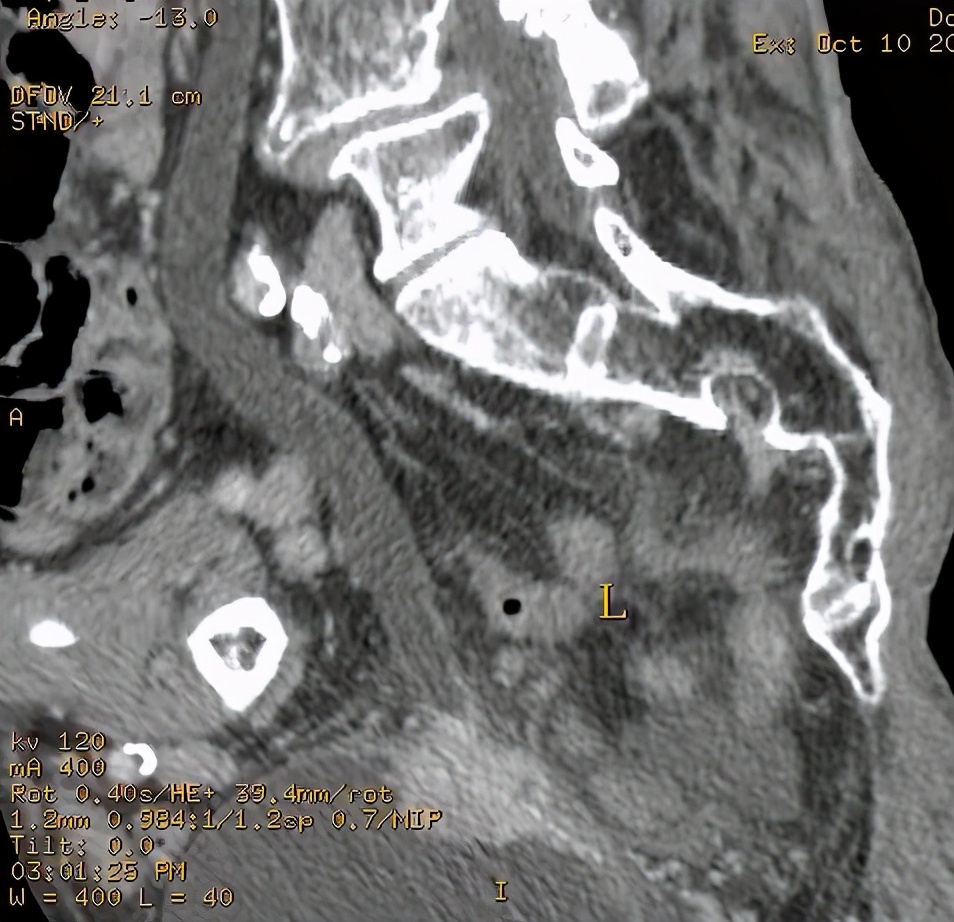

上图所示:38岁男患,血尿待查。CT尿路造影检查示膀胱左后壁增厚,有强化表现,阻塞左侧输尿管膀胱入口处,致左肾积水、左侧输尿管扩张。考虑膀胱癌可能。